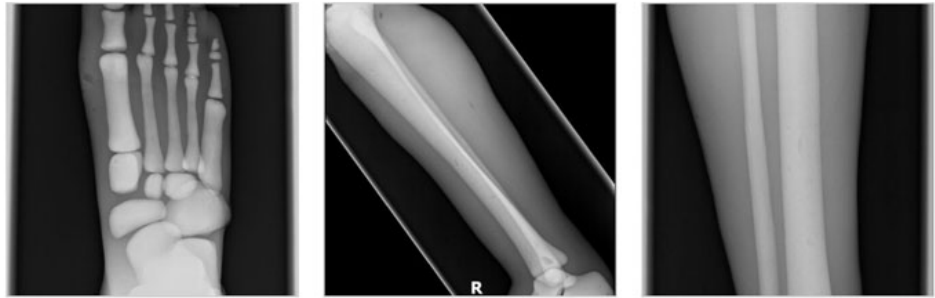

成人腿部模體,用于 X 射線 CT 和超聲波的成人腿部(肌肉)模型是一種基于人類男性腿部平均解剖結(jié)構(gòu)設(shè)計的逼真模型。它具有所有基本的骨骼和

軟組織特征,使其成為學(xué)習(xí)、研究和測試醫(yī)學(xué)成像設(shè)備的理想工具。 模體可用于研究不同方向和定位技術(shù)的多種診斷性 X 射線 CT 和超聲程序。根據(jù)

要求,該產(chǎn)品可以根據(jù)不同的病理進行定制,也可以用于特定的培訓(xùn)應(yīng)用。 模體尺寸:965.2 x 254 x 177.8 毫米,重量:12kg(約)